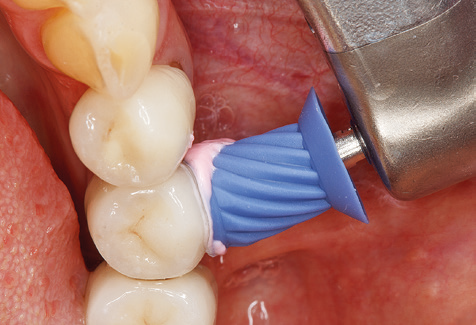

Fig. 4: Flexible probes with millimetre markings are recommended for the probing of dental implants (e.g. Colorvue Kit PCV11KIT6, Hu­Friedy). – Fig. 5a and b: A straight working tip (1P, W&H Dentalwerk Bürmoos GmbH) is a suitable instrument for use on all natural teeth. – Fig. 6: Curved working tips (3Pr/3Pl, W&H Dentalwerk Bürmoos GmbH) lend themselves to the processing of difficult-to-reach areas of the tooth and root surfaces (e.g. furcations). – Fig. 7: The tapered, hexagonal implant cleaning tip (1I, W&H Dentalwerk Bürmoos GmbH) permits atraumatic and efficient cleaning of the crown and abutment surfaces. – Fig. 8: Titanium and carbon curettes are suitable instruments for the manual cleaning of the implant surfaces.

Of course, working tips for the cleaning of implant surfaces are also indispensable for SPT in patients fitted with implants. The implant cleaning attachment on the system used here is characterised by its tapered, hexagonal design. This design allows light, atraumatic penetration of the peri-implant pocket and displays a good cleaning performance (Fig. 7).

Following machine cleaning of the tooth and implant surfaces, the surfaces of the natural teeth are cleaned manually using standard hand instruments. When performing manual cleaning, particular attention must be given to maintaining the correct angle of application, appropriate sharpness, good support and working with the curette from apical to coronal. Either titanium or carbon curettes should be used for post-cleaning of the implant structures (Fig. 8). In addition to the use of ultrasonic devices, power jet devices can also be used in conservative dentistry. However, it must be taken into consideration that these procedures are not suitable for removing hard deposits and thus they cannot replace the use of hand instruments and ultrasonic instruments completely. In all cases, cleaning is followed by mechanical polishing of the accessible tooth and implant surfaces with polishing cups and polishing compounds (Fig. 9).